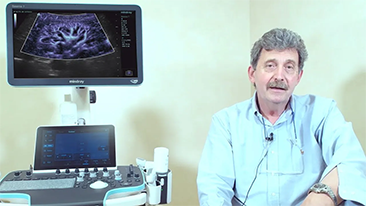

???19 - ??? ????? ?? ??

??? ????? ?? ??? ???? ??? ???? ??? ????, ?? ?? ??(PPE)? ??? ??, ? ??, ??? ?? ??? ???? ??? ?? ??? ??????. ???? ???? ??? ??? ??? ?? ??? ???? ?? ?? ?? ???? ?? ?? ??? ?? ???? ???? ?? ?? ?? ??(POC) ? ??? ??? ? ? ?????.